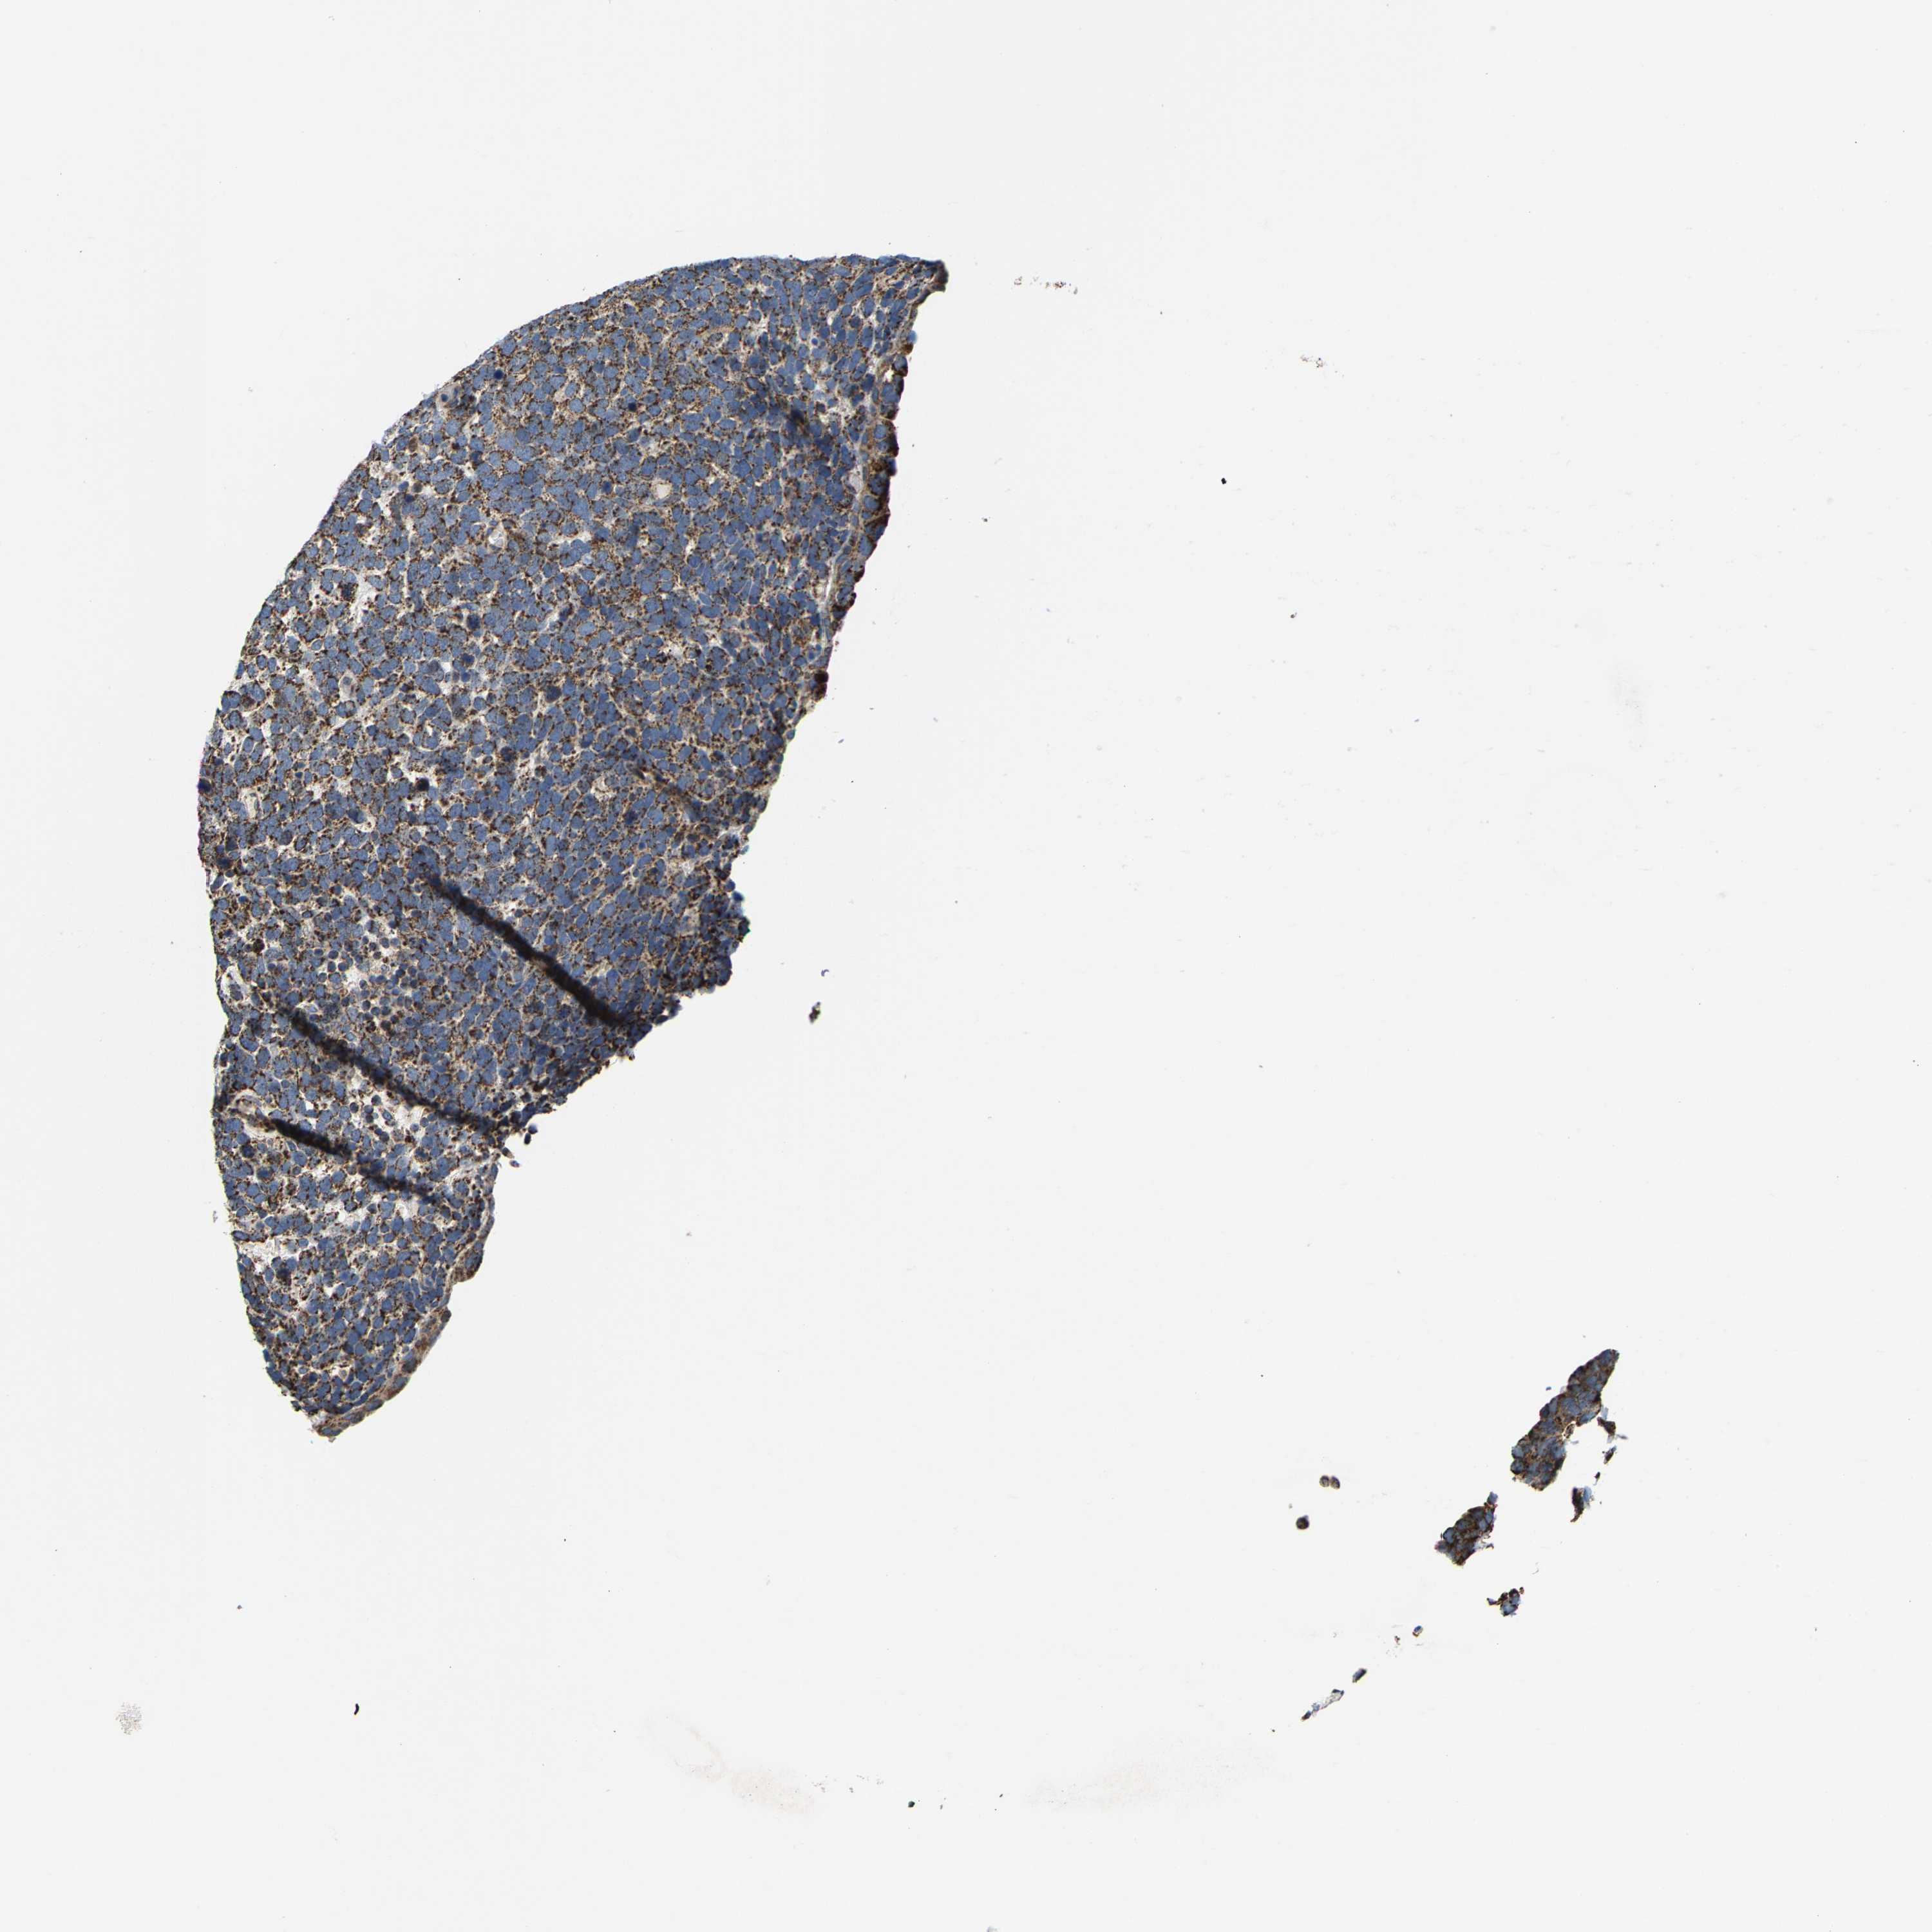

UROTHELIAL CANCER - Protein expressioni

A mouse-over function shows sample information and annotation data. Click on an image to view it in a full screen mode. Samples can be filtered based on level of antibody staining by selecting one or several of the following categories: high, medium, low and not detected. The assay and annotation is described here.

Antibody stainingi

Antibody staining in the annotated cell types in the current human tissue is reported as not detected, low, medium, or high, based on conventional immunohistochemistry profiling in selected tissues. This score is based on the combination of the staining intensity and fraction of stained cells.

Each image is clickable and will lead to virtual microscopy that enables deeper exploration of all samples and also displays staining intensity scores, fraction scores and subcellular localization as well as patient and tissue information for each sample.

Antibody HPA020543

Antibody HPA020549

Staining

High

Medium

Low

Not detected

Intensity

Strong

Moderate

Weak

Negative

Quantity

>75%

75%-25%

<25%

None

Location

Nuclear

Cytoplasmic/membranous

Cytoplasmic/membranous,nuclear

Urothelial carcinoma, Low grade

Urothelial carcinoma, High grade